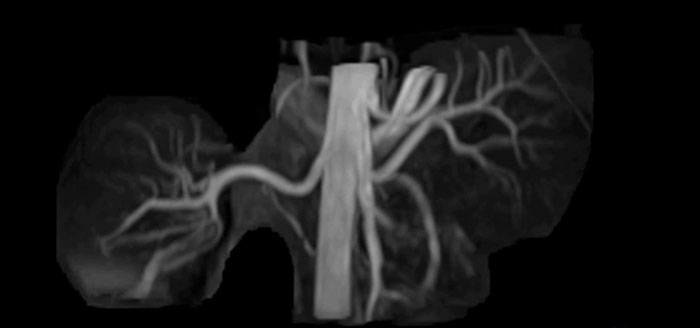

Non-contrast MRA of renal arteries

Imaging the renal arteries without contrast agent on Prodiva 1.5T.

TRANCE MIP

eMIP native Angio RL